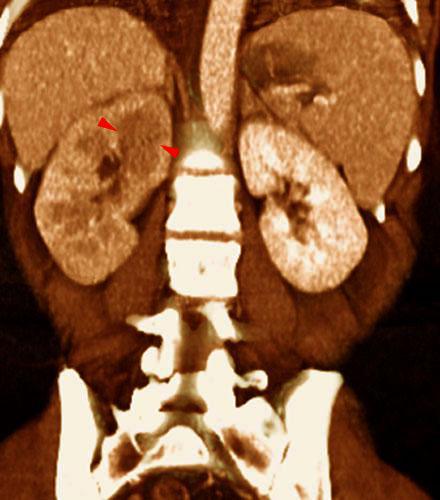

Pielonefritis aguda 1

VR seccional. Visión coronal anterior. Riñón derecho aumentado de tamaño y con disminución de la contrastación. Área hipodensa (puntas de flecha) en su polo superior